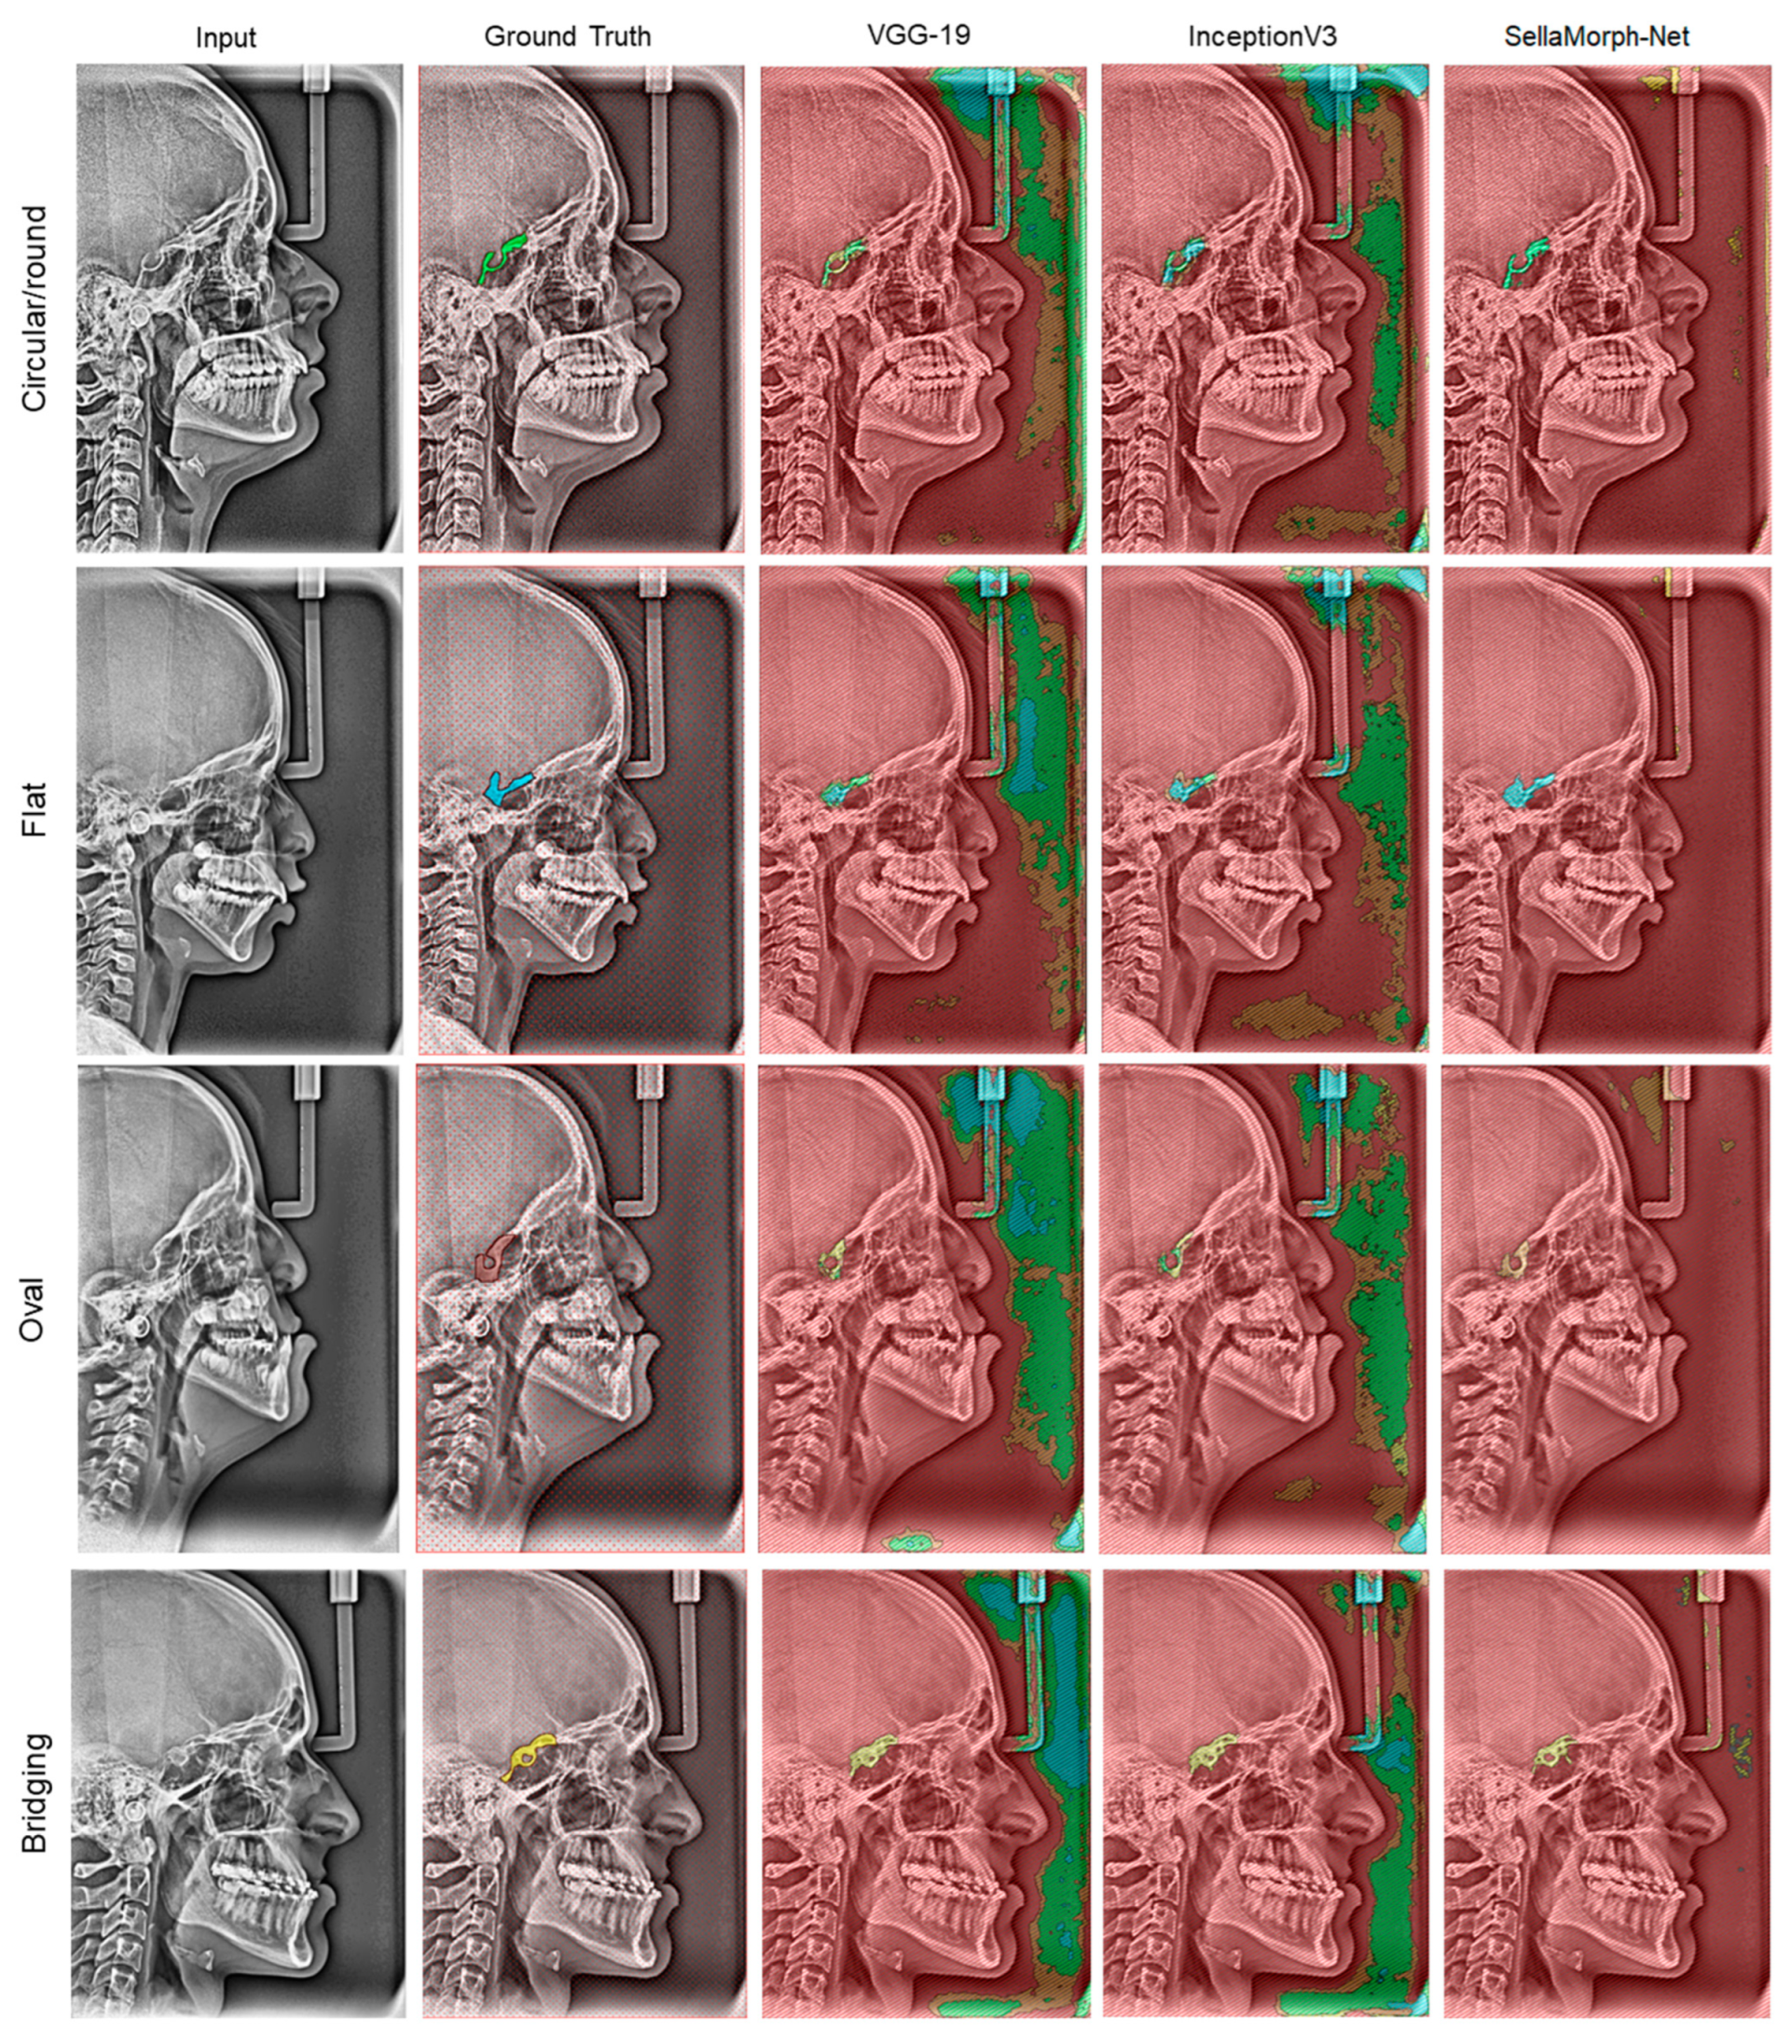

In order to assess the qualitative performance and efficacy of the suggested method, the study presents visual outcomes for the segmentation of regular, moderately altered, and complexly altered ST structures in Figure 8, Figure 9 and Figure 10. These structures were selected based on the cephalometric dataset’s complexity. In addition, the study compared the accuracy of our hybrid SellaMorph-Net model against VGG-19 and InceptionV3. The results demonstrated that while VGG-19 and InceptionV3 were able to provide an approximate ST type, they were unable to predict the detailed morphological structures of ST.

On the other hand, SellaMorph-Net predicted the ST types with high precision for all three dataset subgroups. Furthermore, the complex altered ST structure in Figure 10 was evaluated, and it was found that SellaMorph-Net predicted the edges of these complex altered categories with greater accuracy and smoothness than the other two models. Further, the proposed model accuracy is validated using 400 cephalometric dataset images available publicly, and the results show the significant performance of the proposed hybrid model in the discussion section (Table 7).

The figures presented in this study demonstrate the efficacy of the proposed method in segmenting complex non-linear structures of the ST in lat ceph radiographs. The segmentation was successful for various classes of ST, including bridging, circular, flat, and oval in severely anomalous structures, indicating its potential for clinical prognostics. Additionally, the segmentation of the Sella was conducted on a dataset that included regular and complex subgroups, allowing for the evaluation of dataset combinations. The study utilised statistical methods such as mean IoU (Jaccard Index) and Dice Coefficient (Equations (5)–(8)) to evaluate the performance of the proposed and pre-trained models. Furthermore, the accuracy and pixel-wise IoU of each architecture were compared with determine which performed better.

Figure 8. Qualitative results of VGG-19, InceptionV3, and proposed hybrid SellaMorph-Net on regular Sella Turcica subgroup dataset.

Figure 9. Qualitative results of VGG-19, InceptionV3, and proposed hybrid SellaMorph-Net on moderately altered Sella Turcica subgroup dataset.